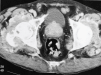

Fig. 2. Tomografía axial computarizada (TAC), erosiones y lesiones líticas con roturas de cortical a nivel de cuello femoral con importante masa de tejidos blandos periarticular.